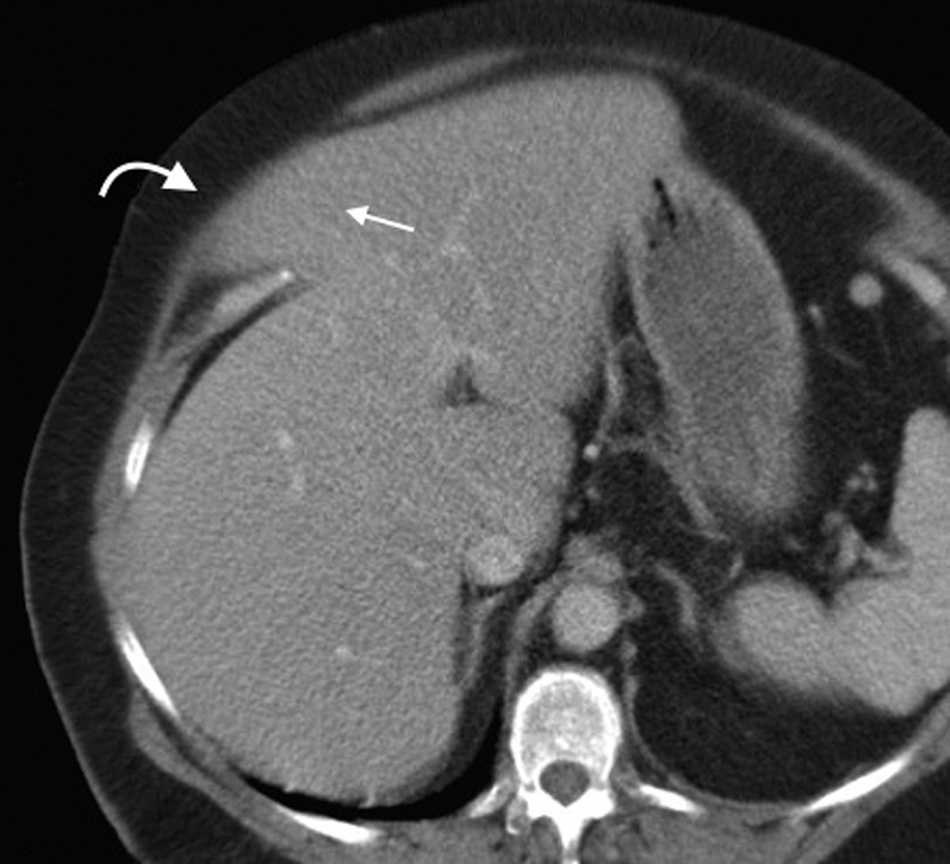

El contenido est?? relacionado con los diferentes sitios de debilidad de la pared. A nivel epig??strico se encuentra una herniaci??n del antro g??strico, del l??bulo hep??tico izquierdo (fig. 14) o de la ves??cula biliar (fig. 15). Por su parte, dentro de las umbilicales puede haber grasa peritoneal, asas intestinales, implantes metast??sicos (n??dulo de la hermana Mar??a Jos??) (fig. 16) o l??quido asc??tico (fig. 17). En la hernia de Spiegel suele visualizarse grasa y asas intestinales, mientras que las obturatrices muchas veces son descubiertas porque el paciente presenta un cuadro de obstrucci??n intestinal mec??nica que ayuda al diagn??stico. En cuanto a la lumbar, se puede herniar grasa, el polo renal o el l??bulo hep??tico derecho (fig. 18). En el caso de la inguinal, esta tiene un contenido muy variado, aunque la grasa peritoneal y las asas son los m??s frecuentes (fig. 19). Adem??s, puede herniar ??rganos intrapelvianos, como la vejiga (cistocele) (fig. 20) o el ap??ndice (hernia de Amyand)20 (fig. 21), y si se produce la herniaci??n del ap??ndice dentro del canal crural, se denomina hernia De Garengeot9 (fig. 22). Finalmente, en las eventraciones se observan asas de intestino delgado y grueso, ri??ones trasplantados (fig. 23) y vejigas (fig. 24).